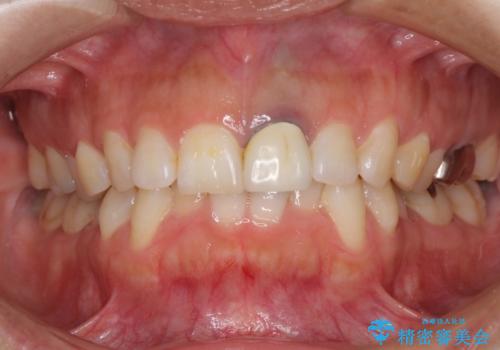

- 前歯をメタルの被せものにしており、セラミックに変えるのを希望された患者様です。

土台も金属だったため、歯がかなり黒く変色していました。

色は完全にとるのが不可能であることをご了承頂いた上で、土台と被せものの治療を行いました。

今回は歯自体が黒くなって歯茎から透けて見えている黒ずみのため、セラミック治療で改善させることは困難だというお話をしました。その上でできる範囲できれいに治療することになりました。